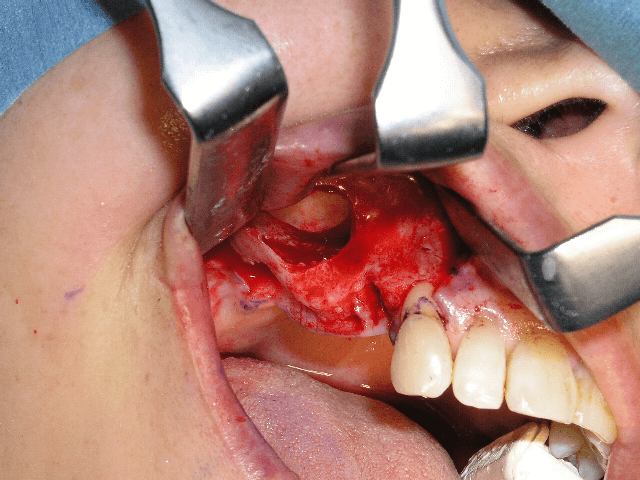

1983年に東京歯科大学が日本で最初にオッセオインテグレーテッドインプラントの概念とその治療法を紹介して以来、口腔インプラント療法は急速な進歩を遂げ、現在では、咀嚼障害や審美障害の改善手段として、長期間にわたる良好な治療成績が確認されています。千葉歯科医療センター口腔インプラント科では、近年、ますます複雑、多様化する患者様のニーズに応えるため、最新の設備や充実したスタッフを配備し、安心・快適・便利を実感できる診療科をめざしています。また、インプラント埋入手術時の鎮静法の併用、基礎疾患を持っている患者様の全身管理下での処置、骨移植、口腔内軟組織移植等の関連手術を行う設備体制を整え、大学医療機関の特色と利点を最大限に生かした治療を心がけています。

1~2本と歯の欠損が少ない場合でのインプラント治療は、従来の治療法(ブリッジや入れ歯)と比較して両隣の歯を削ったりする必要がなく、残っている歯に負担をかけないですみます。また、前歯の治療においては隣在歯と調和のとれた高い審美回復が必要とされることから、骨と粘膜の高度なマネージメントが必要とされます。口腔インプラント科では、高いレベルの審美修復治療の結果を達成するよう専門スタッフが対応しています。

部分入れ歯や総入れ歯などを使う必要がある歯の欠損に対するインプラント治療では、入れ歯と比較して違和感が少なく、咀嚼や発音などの機能回復が期待できます。また、欠如部以外の残存歯の治療が必要になる場合も、初診時からメンテナンスに至るまで一貫した包括的治療を行っています。また、インプラント埋入部位の骨が不足していたり、その他の要因でインプラント療法を断念されていた患者様に対しても、各分野の専門スタッフが高度な診断技術により対応をしています。